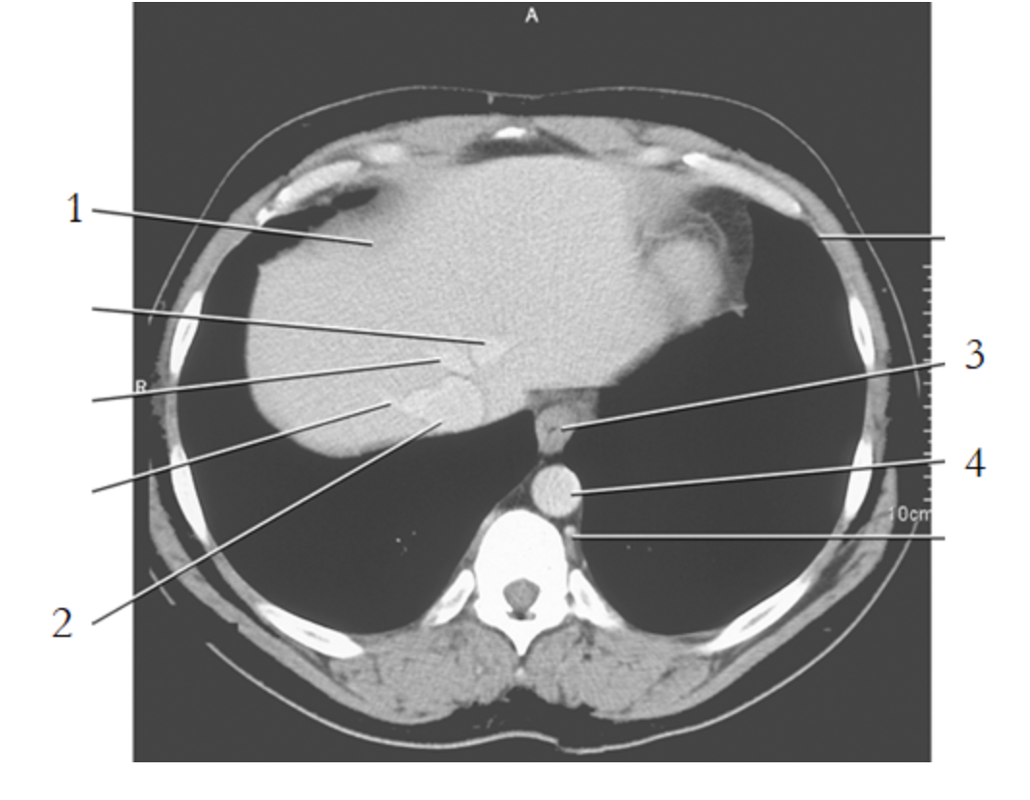

2

IV

11

celiac axis

12

splenic artery

15

portal vein

19

left renal vein

1

liver

3

esophagus

stomach

spleen

9

crus of diaphragm

8

IVC

13

pancreas tail

16

kidney

14

gallbladder

4

left renal artery

25